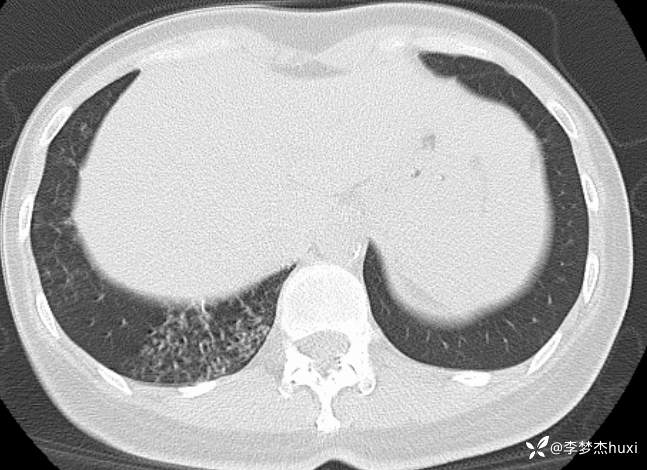

女性53岁,腮腺癌术后反复咳嗽、咳痰,胸部CT以树芽征为特点改变,最可能的是哪种疾病

【现病史及既往史】: 1.患者中年 女,患者于入院前5天无明显诱因出现咳嗽,咳痰,为黄绿色痰,量少,不易咳出,伴发热,最高体温不详,伴周身乏力,无胸痛,无呼吸困难,无恶心、呕吐,无腹痛、腹泻,无抽搐及意识障碍,院外未诊治,症状无好转,今患者及家属为进一步诊治前来我院就诊,门诊查胸部CT:右肺上叶占位性病变应考虑,右肺上叶空洞;右肺下叶占位?双肺炎症,支气管炎?右肺门淋巴结增大,双肺实性结节,纵隔结节,主动脉及冠状动脉钙化,右侧乳腺结节?建议结合超声,建议结合临床复查。门诊以“肺炎”收入院 。

3.查体:T37.3℃,P84次/分,R19次/分,BP130/80mmHg。神清,呼吸平稳,浅表淋巴结不大,双肺叩清音,双肺可闻及少许湿性啰音,心率84次/分,律齐,无杂音。腹部平坦,软,无压痛,无反跳痛及肌紧张,肝脾肋下未触及,双下肢无水肿。

【临床诊断】: 1.肺炎

【治疗经过及结果】:抗感染治疗